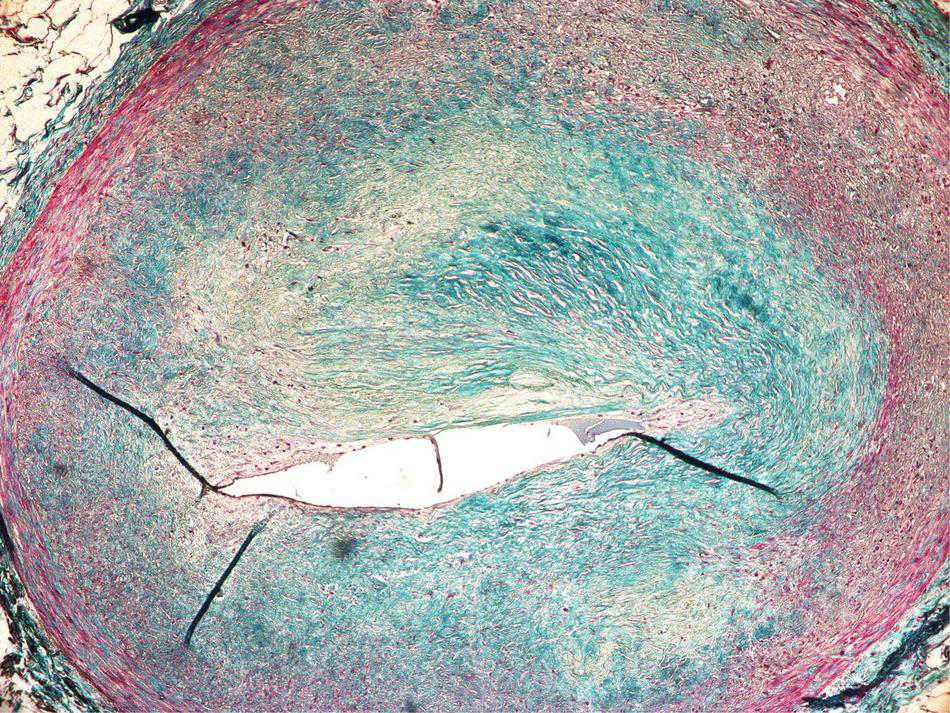

Occluded, atherosclerotic left anterior descending artery with fibrous cap and a lipid core plaque.

The small arteries within the region irradiated with 25 Gy presented with sub-intimal fibrosis, and symptoms of intimal changes such as endothelial cell enlargement and the presence of scattered lymphocytes inside thickened intima. The endothelial layer remained intact, and the lumen was preserved (Figure 7).

FIGURE 7

Subendothelial fibrosis of epicardial coronary artery found within the irradiated region.

The initial concept assumed that the biological mechanism of STAR would be similar to RFA through the development of transmural fibrosis in the region of the arrhythmic substrate, and subsequent cessation of electric signal propagation. The clinical experience, however, indicates that STAR induces clinical effects significantly earlier. For example, there are reports of successful electrical storm cessation after STAR (13, 14). Moreover, Kiani et al. found significantly less fibrosis than expected based on the pre-clinical assumptions, despite up to 250 days of follow-up in a total of four explanted hearts (6). As mentioned earlier, a possible game-changing finding was recently published by Zhang et al. (5), suggesting functional changes as a primary mechanism of STAR. If proven to be durable, a significantly different mechanism of treatment could help overcome RFA recurrences. Most importantly this implies a possibility of multimodality treatment, as the irradiated cardiac tissue remains functional and likely sensitive to complementary treatments. This puts into question the use of the word “ablation” when referring to cardiac radiosurgery. As more evidence emerges, it might be more accurate to use the aforementioned “Cardiac SBRT” term, which does not imply bluntly destroying the tissue, but merely associates stereotactic radiotherapy with heart-focused treatment. Another reason to abstain from the “ablation” term would be the effect on small coronary arteries. Despite the expected anti-vascular effect in radiotherapy with fraction doses exceeding 15 Gy (15), we have found that the smaller vessels within the 25 Gy volume remained functional (Figure 7). Although the histopathological examination has shown clear signs of degenerative changes, it is difficult to differentiate between radiation-induced and pre-existing changes, as the patient was suffering from ischemic cardiomyopathy.

Our findings support the theorem that the anti-arrhythmic effect can occur and be persistent over time despite the lack of RFA-like scar formation. Moreover, the microscopic analysis revealed that up to 12 months after RT, there was no significant occlusion of the small vessels within the high irradiation dose region of the patient’s heart, suggesting that coronary artery sparing might be of less importance than previously assumed by some of the authors.